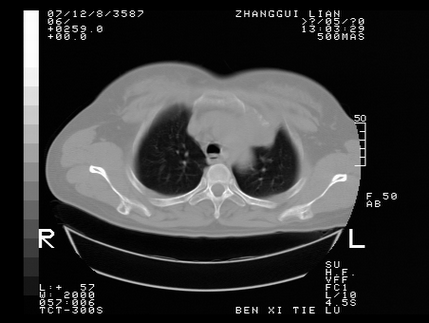

标题: CT10818:男,73,TB病史,现病史肺炎及直肠CANCER术后 [打印本页]

标题: CT10818:男,73,TB病史,现病史肺炎及直肠CANCER术后

这个请版主删除掉,这个病例我发过的,发重了,此人病史是,f,46y,胸疼,无其他原因就诊

左侧中央型肺癌伴阻塞性肺炎\\不张,左侧前上纵隔亦增宽,建议上传纵隔窗除外淋巴结转移.

考虑:左侧中央型肺癌伴阻塞性肺炎,纵隔淋巴结转移。

1)考虑为:左侧中央型肺癌伴阻塞性肺炎,纵隔淋巴结转移。2)双侧少量胸腔积液。3)心包积液。

左侧中央型肺癌伴阻塞性肺炎,纵隔淋巴结转移。

考虑左侧中央型肺癌伴阻塞性肺炎,纵隔淋巴结转移。